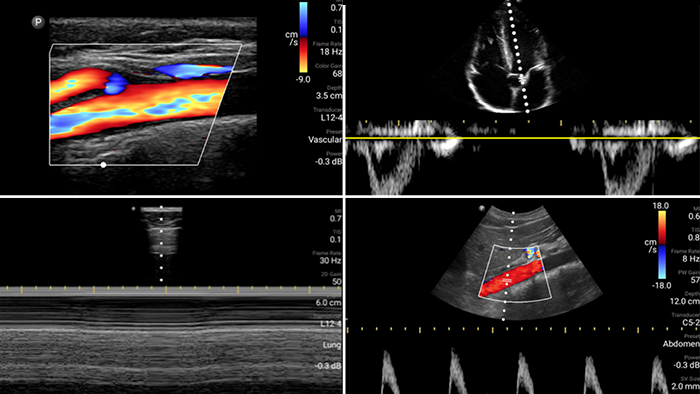

Beurteilen, diagnostizieren und behandeln Sie Ihre Patienten in Minuten mit einer Multi-Point-POCUS-Untersuchung.

Lumify kann helfen, Patienten schneller zu beurteilen und die Diagnosegenauigkeit häufiger Ursachen von Dyspnoe und anderen Lungenerkrankungen zu erhöhen.

Jede Sekunde zählt in der Kardiologie

Herzinfarktpatienten benötigen unmittelbare Versorgung. Mit den kardiologischen Presets von Lumify können Patienten schneller diagnostiziert werden, um ihre Prognose zu verbessern.